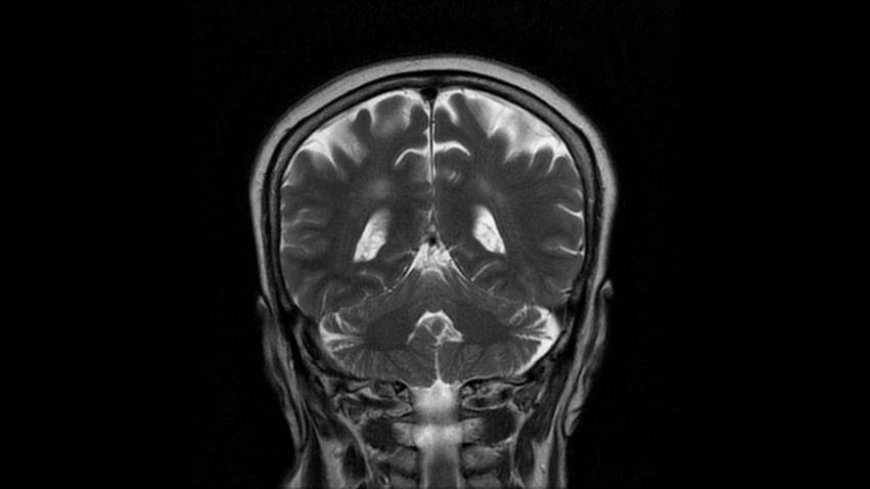

MRI of Brain

Coronal T2